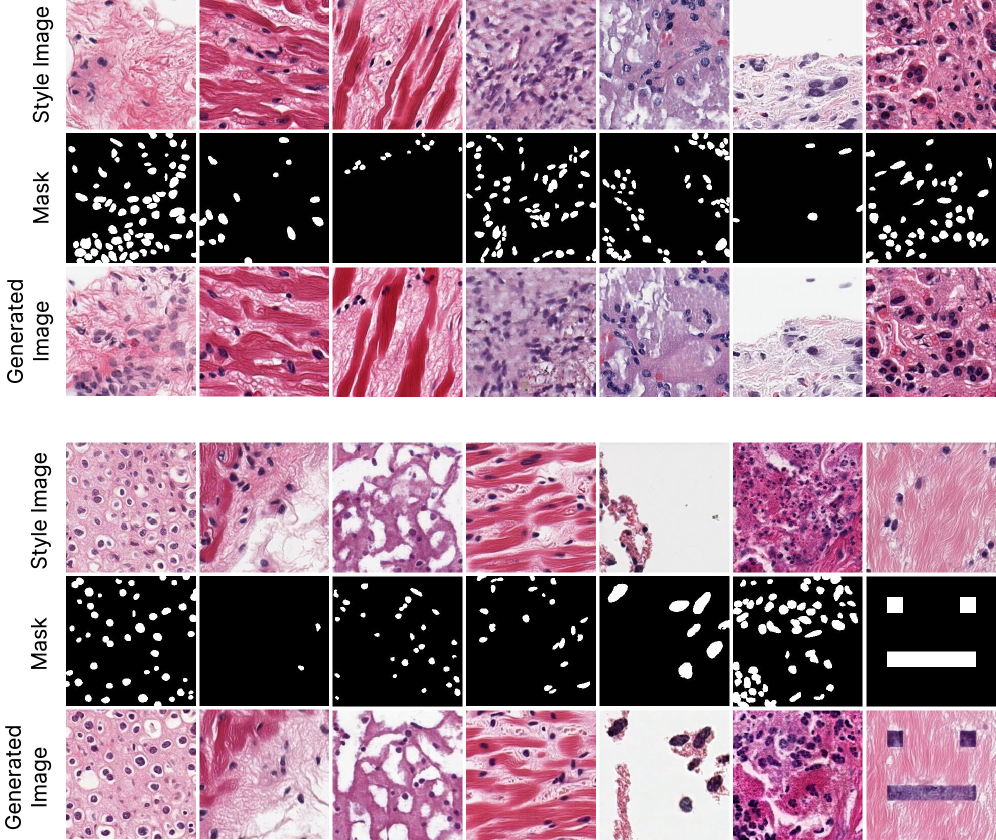

A.7 Controllable generation

Figure 13: PixCell-256 with a cell mask ControlNet. The two sources of conditioning allow for fire control over the generated image: the UNI embedding dictates the style of the generated image while the cell mask guides the cell layout.

PixCell generates images conditioned on an embedding from a self-supervised encoder. Within this framework, we can synthesize variations of a given image but lack further control over the synthesized image content. To introduce the ability to controllably generate images, we employ ControlNets [zhang2023adding], which add image-level control to pre-trained diffusion models.

We train a ControlNet for PixCell-256 to guide generation with a cell layout mask. To construct a training dataset, we utilize a pre-trained CellViT-SAM-H [horst2024cellvit] model trained on 0.5 microns per pixel images. We extract cell masks from 10,000 images of all cancer types from PanCan-30M and train the ControlNet with image, UNI embedding, and mask triplets. The diffusion transformer ControlNet copies each layer of the base transformer, adding an intermediate output linear layer that is zero-initialized to combine the base transformer and ControlNet transformer features [chen2024pixart]. An overview of the ControlNet approach is provided in Figure 13.

Figure 14: Images generated using the cell mask ControlNet. The synthesized samples follow the appearance of the style image, from which the UNI conditioning is extracted, and the cell layout of the reference mask. The UNI conditioning from the style image is not sterile from cell information, and when the two significantly contrast, the generated images fail to follow the mask accurately (top, columns 6-7). The guidance scale used is w=2.5w=2.5.

In Figure 14, we showcase images sampled using the trained cell mask ControlNet. The PixCell-256-Cell-ControlNet model allows for finer control over the generated image. By providing the UNI embedding from a reference image and a target cell mask, we have disentangled the appearance (guided by UNI) and cell layout (guided by the mask) of the generated image. However, this disentanglement is not perfect since the UNI-2h conditioning also encodes some information about the cell count and layout. We observe that in some cases, the clashing control signals lead to images that do not exactly follow the given mask (columns 6-7 of Figure 14). Although we can increase the guidance scale of the ControlNet conditioning, this can lead to potentially unwanted artifacts in the generated images or the model completely ignoring the UNI conditioning, as shown in Figure 15.